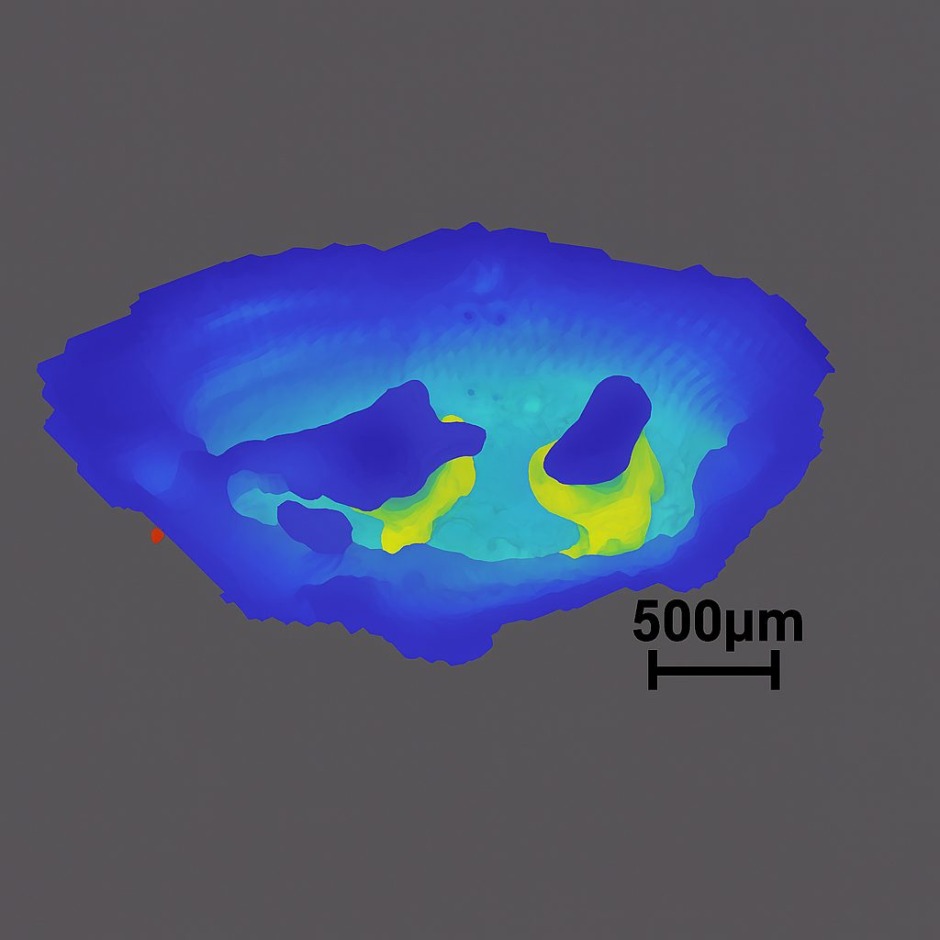

芹田和則准教授らの研究グループが、内耳蝸牛内部の非破壊3D観察に世界で初めて成功しました

早稲田大学大学院情報生産システム研究科 芹田和則(せりたかずのり)准教授、神戸大学大学院医学研究科 藤田岳(ふじたたけし)准教授、柿木章伸(かきぎあきのぶ)特命教授、大阪大学レーザー科学研究所 斗内政吉(とのうちまさよし)教授、大阪大学大学院工学研究科博士課程Zheng Luwei(ゼンルーウェイ)氏らによる研究グループの研究成果がプレスリリースされました。